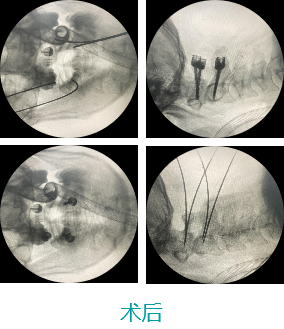

天玑II 辅助颈椎椎弓根螺钉内牢靠术

基本情形:患者男,49岁,枢椎骨折

病例泉源:北京积水潭医院